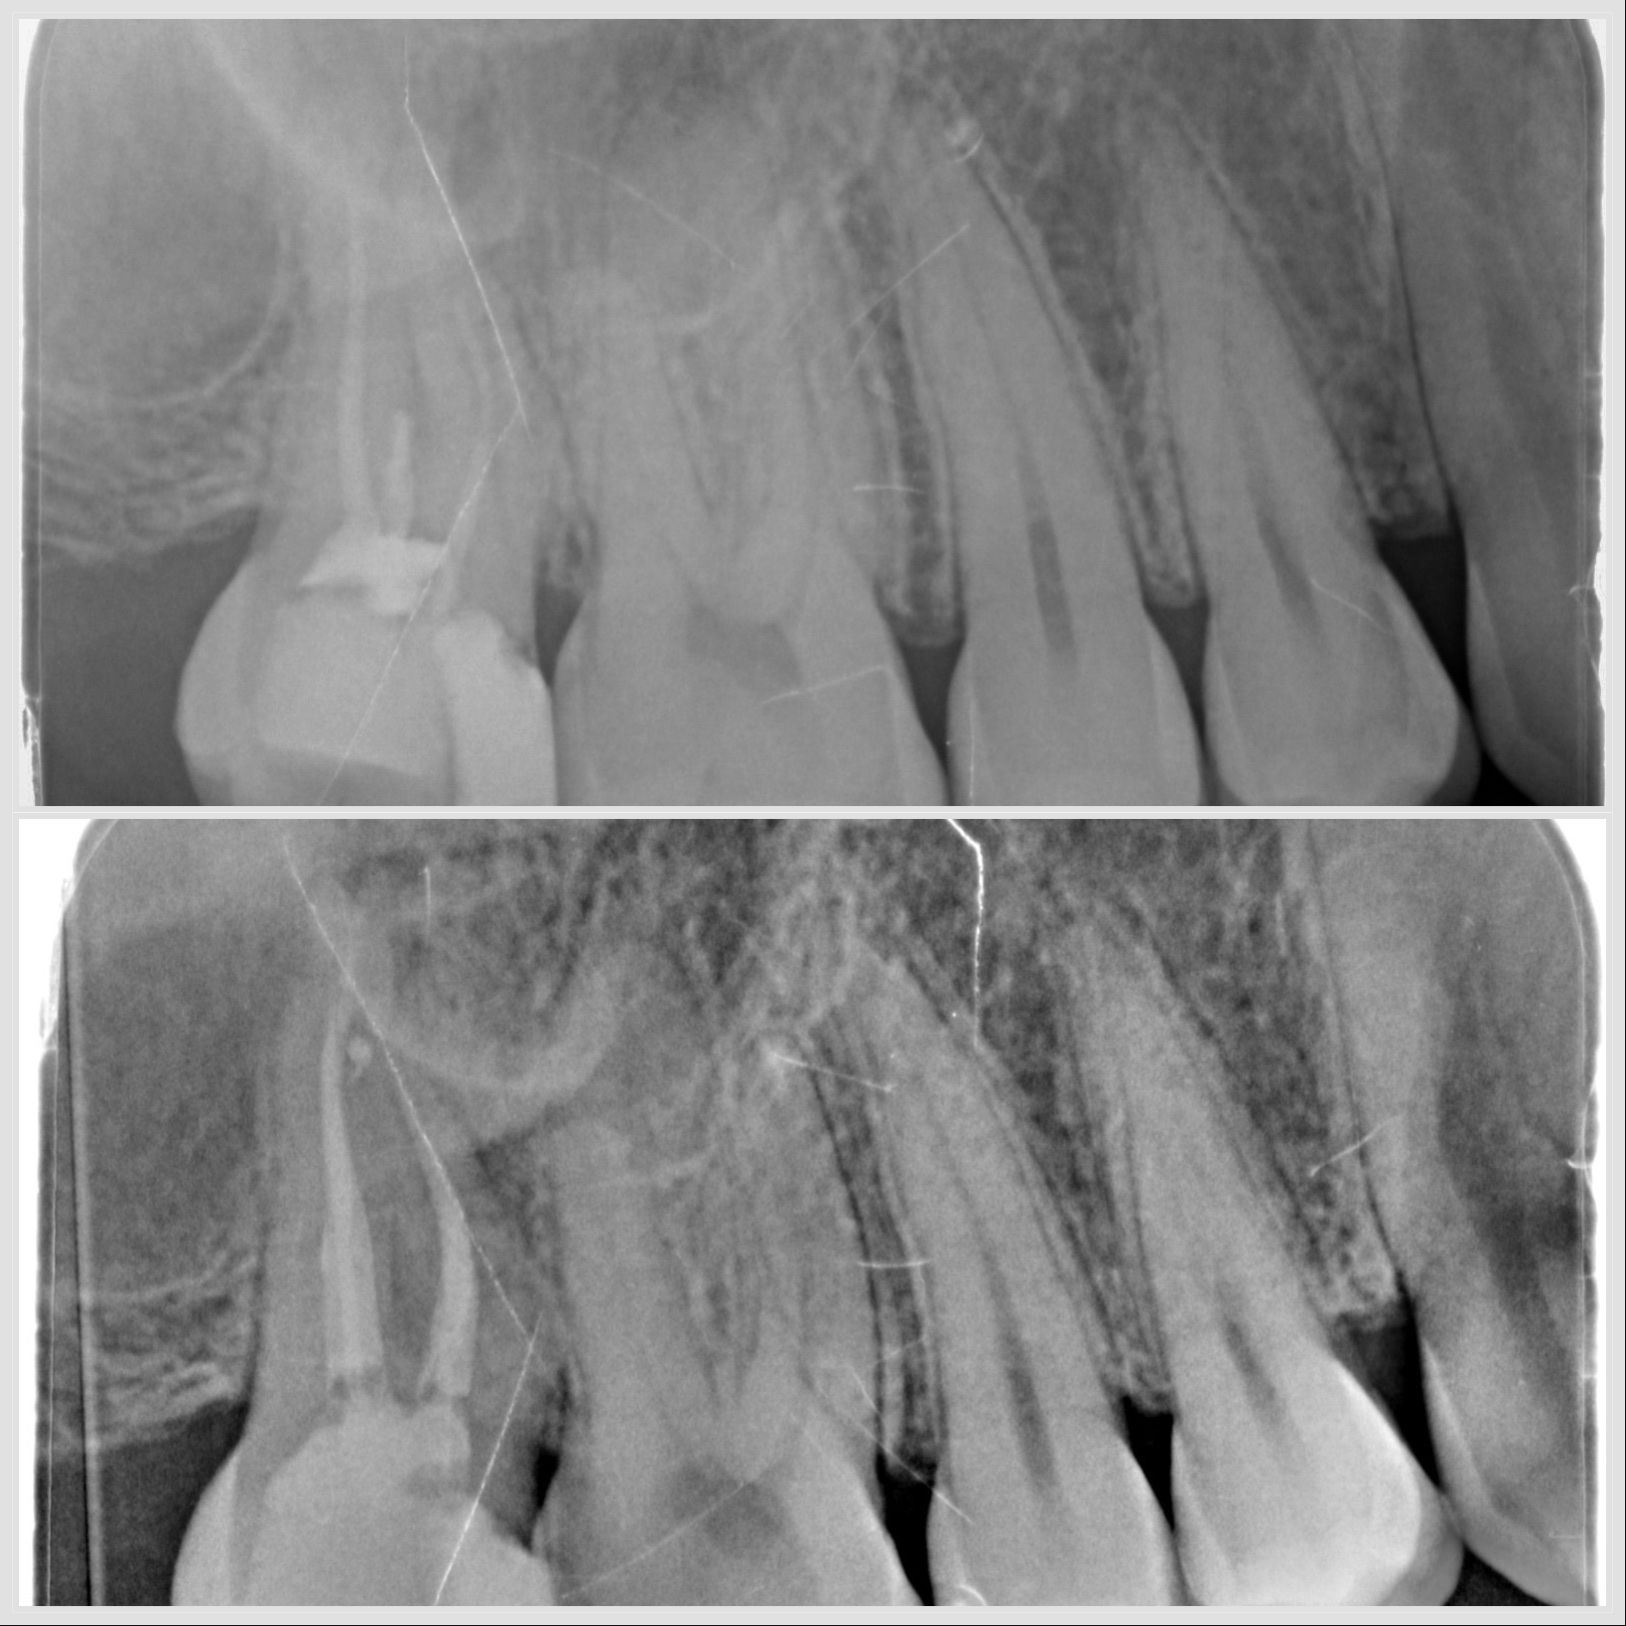

Prémolaire mandibulaire avec trois canaux traitée sous microscope à Apolline Dental Care à Corbeil-Essonnes

Endodontie prémolaire 3 canaux

#endodontie

Traitement endodontique sur prémolaire avec trois canaux réalisé à Apolline Dental Care à Corbeil-Essonnes

Endodontie sur prémolaire à 3 canaux